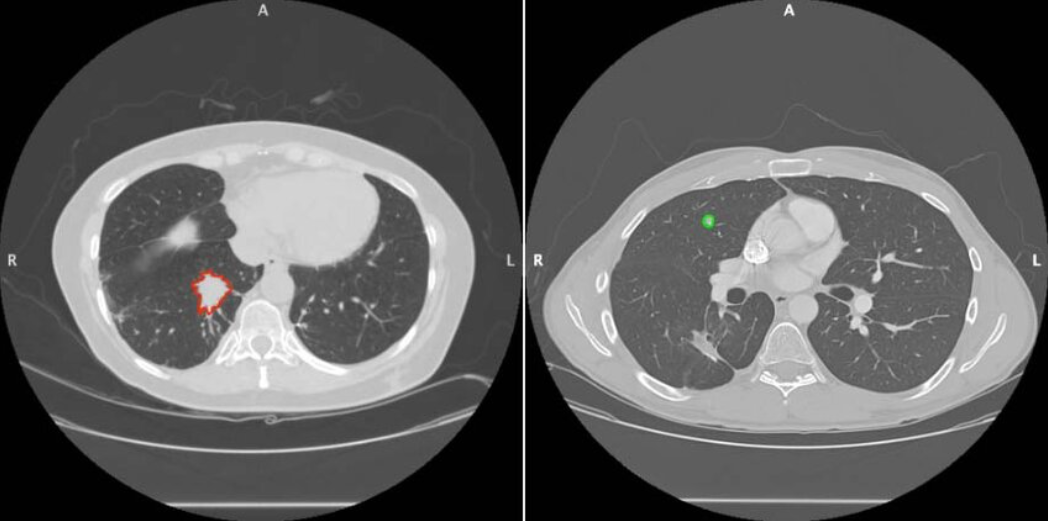

Benign lung tumors are normally discovered when healthcare providers are performing checks for separate issues. This may be during an X-ray or a CT scan, and often, images from CT scans can be used by doctors to determine whether a tumor is benign. If healthcare professionals are concerned a tumor might be cancerous, they might order a PET scan. If more information is required, a bronchoscopy might be performed.

Your healthcare team will then use other information about your nodule to determine if it’s benign. Here are some common indicators of benign lung nodules:

- Small size

- Slow growth

- Higher calcium content

- Smooth, even shape

- Even color